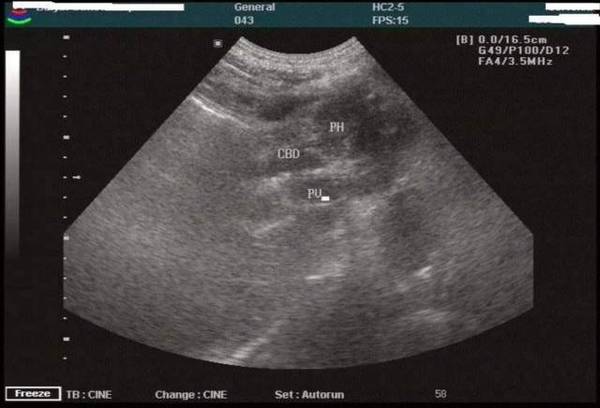

超声检查

想要性价比高又无创的检查?超声绝对是首选。超声检查能明确地发现直径大于 2cm 的胰腺实质性肿块。此外,它还能发现由肿块引起的胆管扩张、胆囊重大和肝内转移。

随着超声技术的进展,过去难以察觉的腹后壁胰腺肿瘤,如今运用纤维胃镜超声探头,便能够直接从胃壁近距离检查。目前超声的胰腺癌术前诊断准确率已高达 92%。